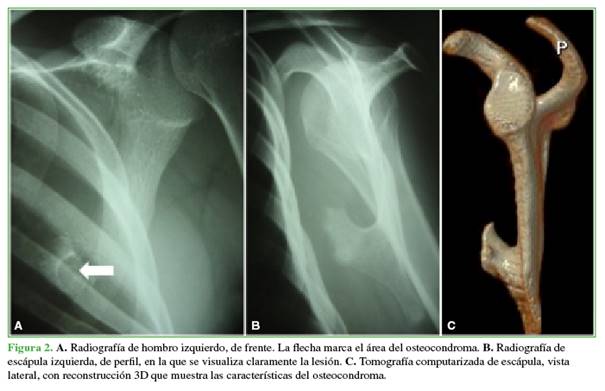

Los estudios complementarios revelaron un osteocondroma ventral cercano al vértice inferior de la escápula (Figura 2). En la tomografía computarizada, se observó la típica imagen en forma de hongo, aproximadamente a la altura de la quinta costilla y una colección líquida hipodensa homogénea de 16 x 5 centímetros. Se descartaron lesiones óseas traumáticas. En una ecografía, también se visualizó la colección líquida, que medía 150 x 30 x 80 mm (Figura 3).